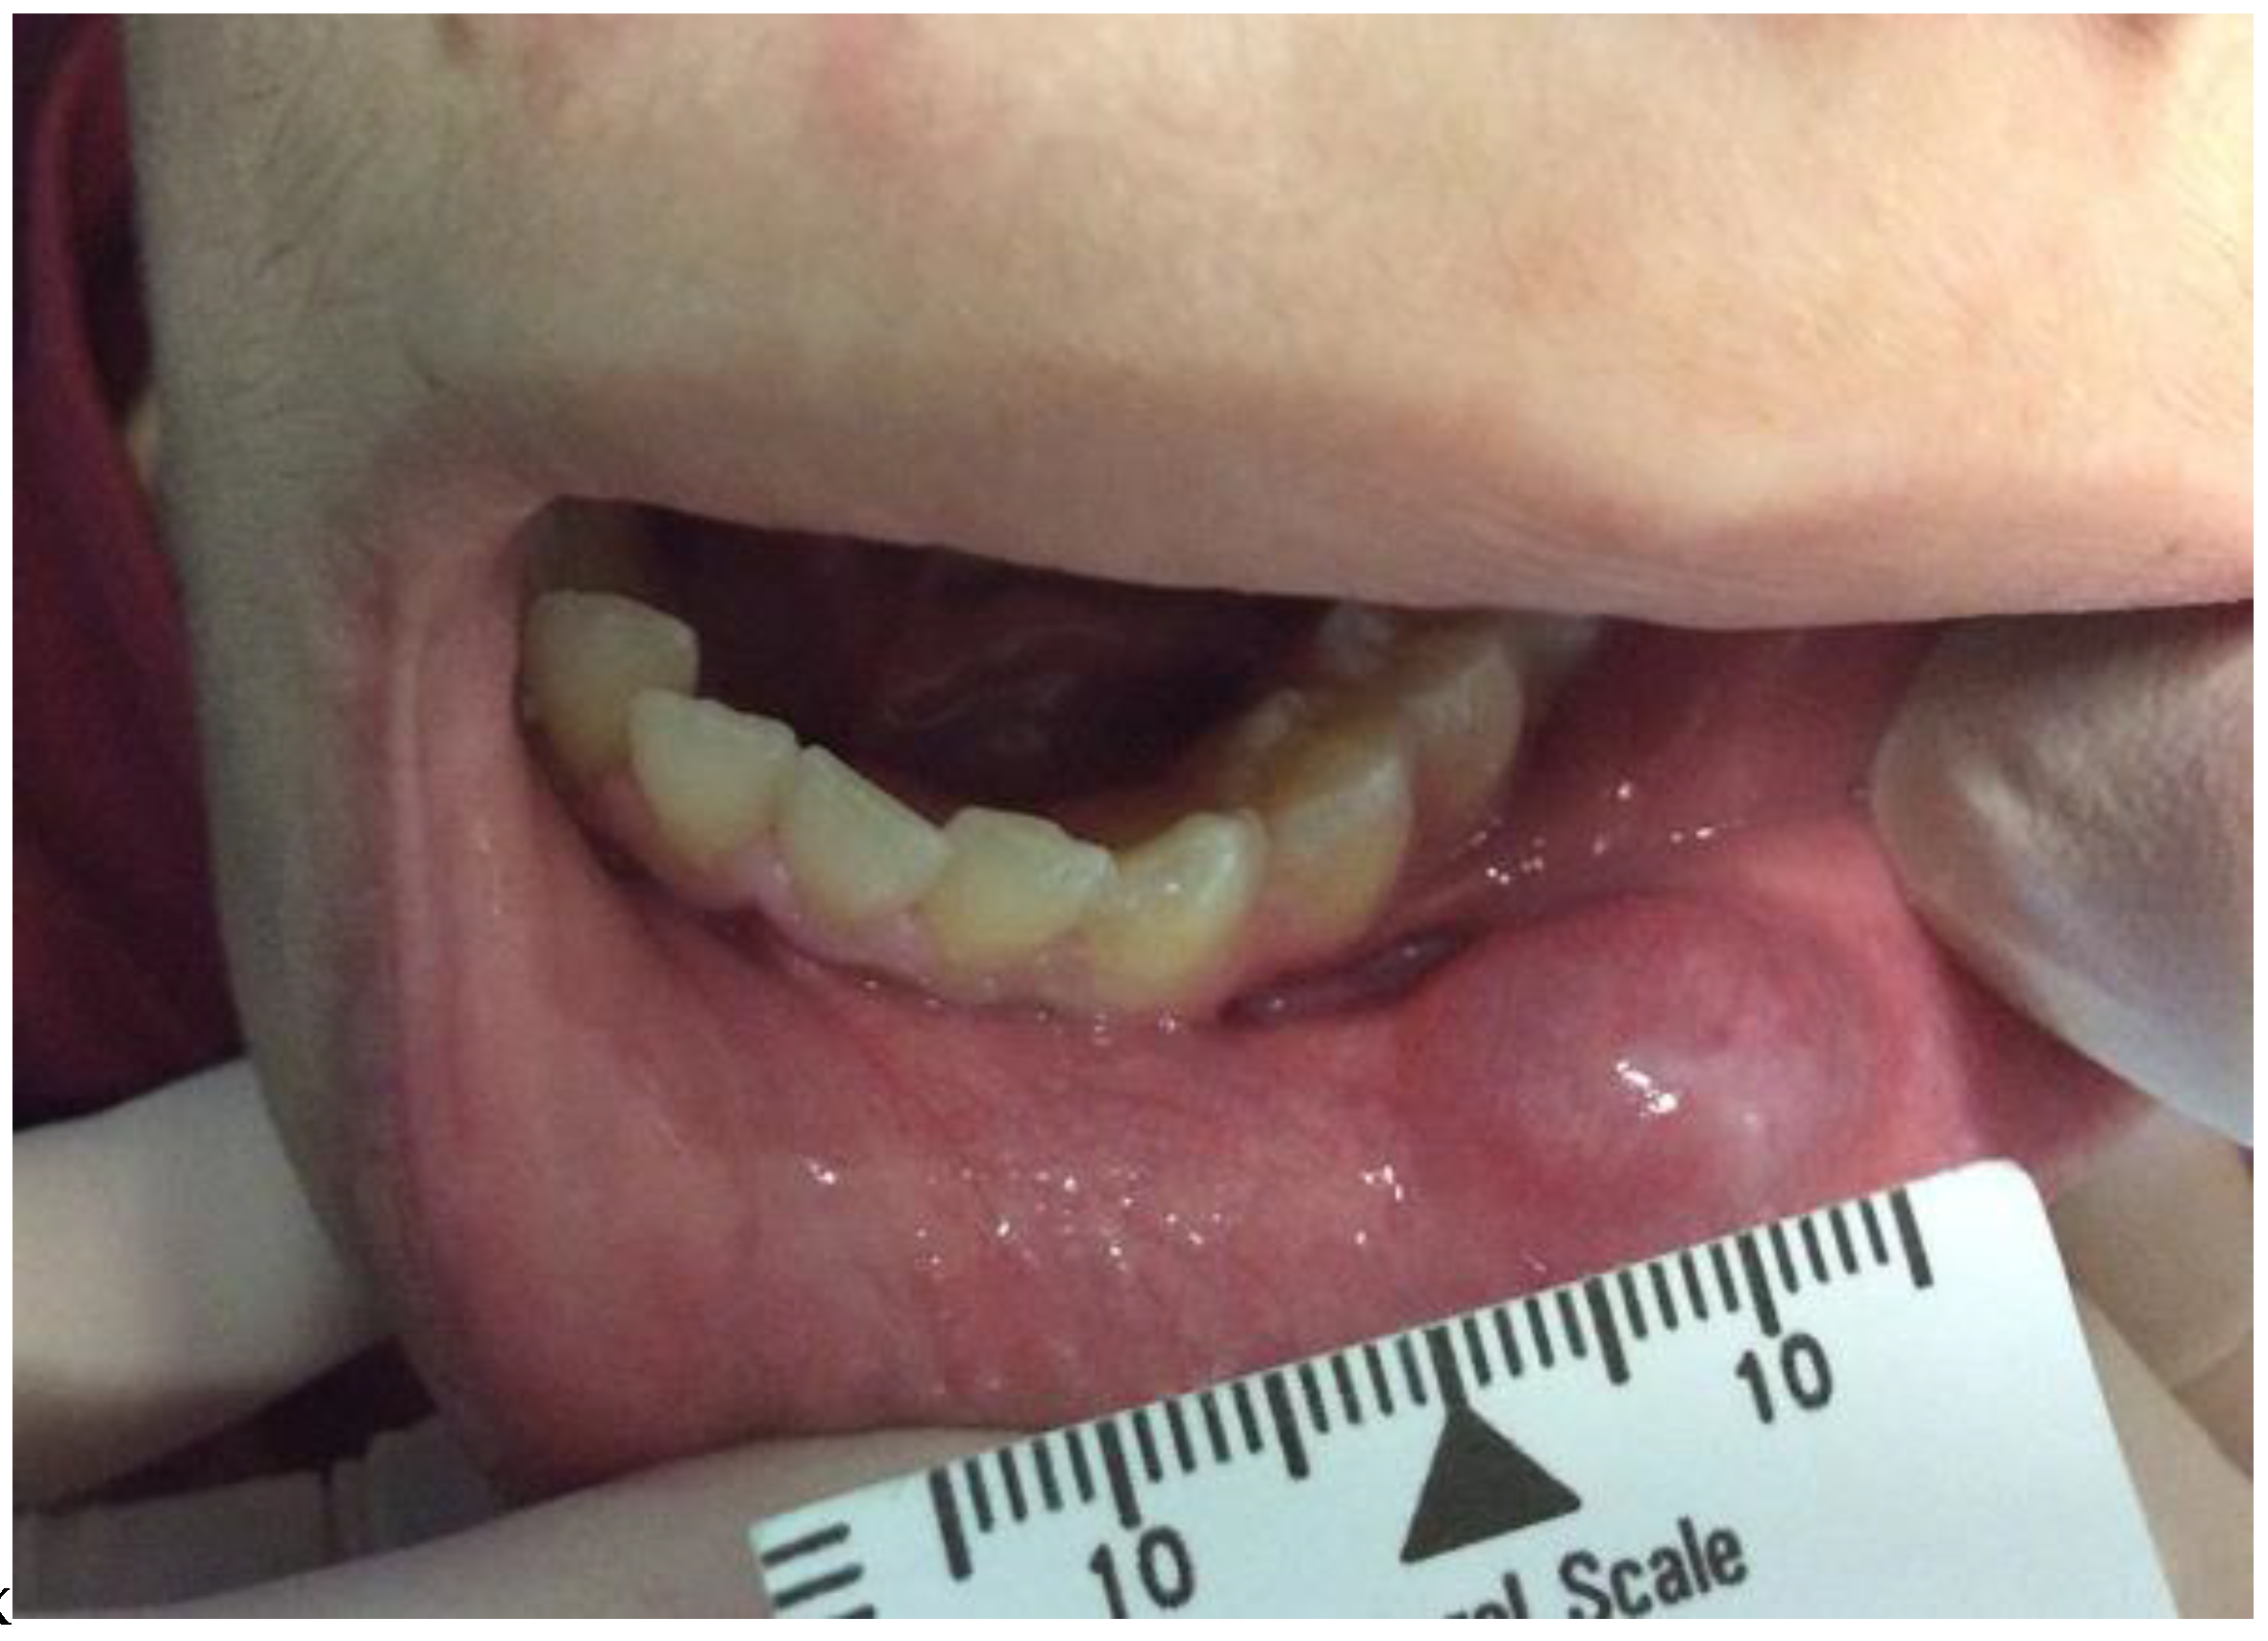

2. Case History

Surgical Procedure